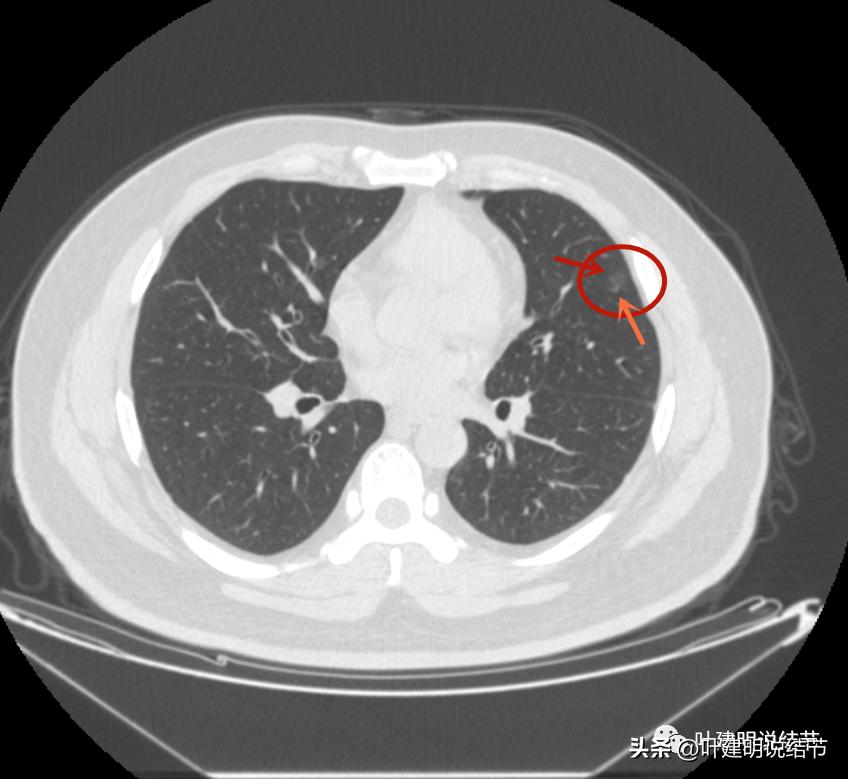

左上病灶1:磨玻璃结节,轮廓清楚伴微血管进入,中间似乎有空泡征,感觉像原位癌或不典型增生;

连续层面看,仍是像恶性范畴的,总体密度低,轮廓清,原来判断腺体前驱病变的意见不变。